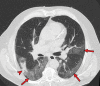

Chest CT has a potential role in the diagnosis, detection of complications, and prognostication of coronavirus disease 2019 (COVID-19). Implementation of appropriate precautionary safety measures, chest CT protocol optimization, and a standardized reporting system based on the pulmonary findings in this disease will enhance the clinical utility of chest CT. However, chest CT examinations may lead to both false-negative and false-positive results. Furthermore, the added value of chest CT in diagnostic decision making is dependent on several dynamic variables, most notably available resources (real-time reverse transcription-polymerase chain reaction [RT-PCR] tests, personal protective equipment, CT scanners, hospital and radiology personnel availability, and isolation room capacity) and the prevalence of both COVID-19 and other diseases with overlapping manifestations at chest CT. Chest CT is valuable to detect both alternative diagnoses and complications of COVID-19 (acute respiratory distress syndrome, pulmonary embolism, and heart failure), while its role for prognostication requires further investigation. The authors describe imaging and managing care of patients with COVID-19, with topics including (a) chest CT protocol, (b) chest CT findings of COVID-19 and its complications, (c) the diagnostic accuracy of chest CT and its role in diagnostic decision making and prognostication, and (d) reporting and communicating chest CT findings. The authors also review other specific topics, including the pathophysiology and clinical manifestations of COVID-19, the World Health Organization case definition, the value of performing RT-PCR tests, and the radiology department and personnel impact related to performing chest CT in COVID-19. ©RSNA, 2020.